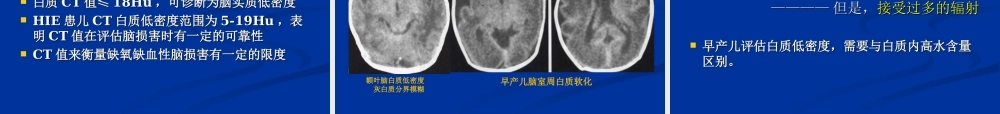

新生儿缺氧缺血性脑病新生儿缺氧缺血性脑病影像诊断影像诊断中国石油中心医院医学影像中心杨景震成人与婴幼儿脑部的成人与婴幼儿脑部的MRIMRI表现表现有很大的差异有很大的差异婴幼儿脑白质髓鞘化过程是其主要特点婴幼儿的脑白质髓鞘化过程,是脑发育成熟的重要标志,一般在1.5岁-2岁完成。概括地讲,髓鞘化过程主要是脑白质的髓鞘形成过程中水含量的变化,这种变化目前只有MRI能够表现出来。即:T1WI信号由低变为高信号;T2WI由高变为低信号。这种变化是按照一定的部位依次出现,称为婴幼儿脑正常髓鞘化过程。一般多在18个月左右时,其脑的MRI影像表现已经接近成人脑。值得强调,在某些部位,例如,三角区后方的脑白质成熟较慢,T2WI片状的高信号可以持续到2岁以上甚至成人。正常成年人脑部正常成年人脑部MRMR图像图像新生儿与成人信号相反新生儿与成人信号相反,,随月份变化随月份变化..3-63-6月月:T1WI:T1WI灰白质等信号灰白质等信号9-189-18月月:T2WI:T2WI灰白质等信号灰白质等信号婴幼儿出生前婴幼儿出生前((胚胎胚胎55月月))至至1818月月,,髓鞘发育最快髓鞘发育最快,18-,18-2424月基本接近成人水平。月基本接近成人水平。髓鞘发育顺序:足侧→头侧髓鞘发育顺序:足侧→头侧中央→周围中央→周围背侧→腹侧背侧→腹侧感觉→运动感觉→运动婴幼儿脑组织MR信号足月新生儿的磁共振T2WI足月新生儿的磁共振T1WI脑部脑部DWIDWI正常表现正常表现儿童脑组织儿童脑组织儿童脑组织的特点:脑组织含水量高、细胞不成熟、儿童脑组织的特点:脑组织含水量高、细胞不成熟、白质未髓鞘化白质未髓鞘化较成人具有明显更高的较成人具有明显更高的ADCADC值值不同区域的不同区域的ADCADC值变化很大值变化很大白质区白质区ADCADC值高于灰质区值高于灰质区出生时皮层下白质出生时皮层下白质ADCADC值高于内囊前肢和后肢值高于内囊前肢和后肢皮层和尾状核皮层和尾状核ADCADC值高于丘脑和豆状核值高于丘脑和豆状核除脑脊液以外,随儿童脑组织成熟度的增加,除脑脊液以外,随儿童脑组织成熟度的增加,ADCADC值相应下降值相应下降脑部脑部DWIDWI正常表现正常表现儿童正常脑质(2d)DWI图ADC图1-2月龄4月龄婴儿脑在T1WI、T2WI上的表现8月龄14月龄24月龄成年人婴、幼儿、成人脑在T1WI、T2WI上的表现髓鞘化在髓鞘化在T1WIT1WI的表现部位的表现部位33月月::小脑中脚小脑中脚(3(3月完全月完全))44月月::胼胝体压部、半卵圆中心胼胝体压部、半卵圆中心44--55月...